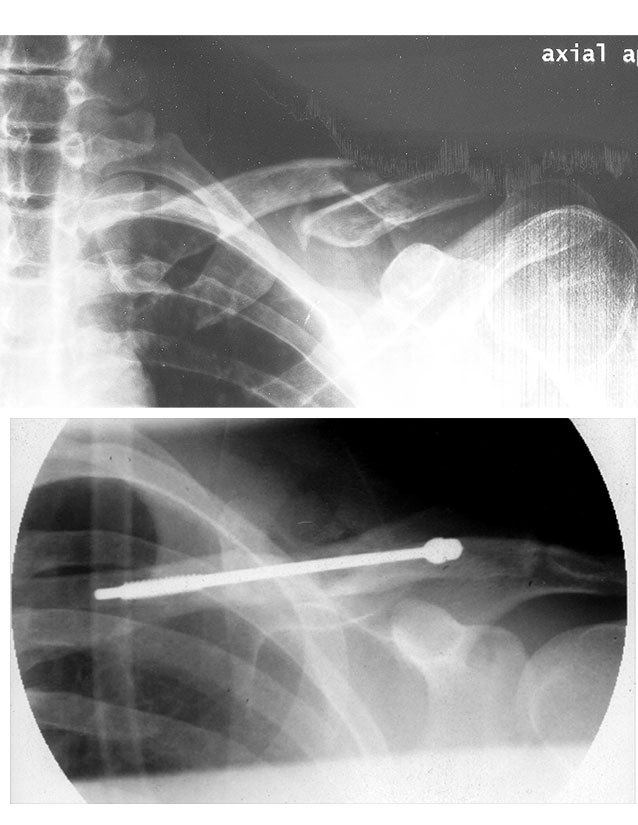

Screws In Collarbone . After being repositioned into their normal alignment, the bone fragments are held in place with special screws and metal plates attached to the outer surface of the. Surgery for a broken collarbone means (1) putting the broken pieces back together and (2) holding them in place with pins or plates and screws. The skin is cut and the collarbone is repositioned to back to where it should be and then held in position with screws and a plate. Open reduction and internal fixation (orif) is a type of surgery used to stabilize and heal a broken bone. You might need this procedure to treat your broken collarbone (clavicle). My collarbone was set with a plate and screws 4 years ago. Broken collarbone surgery usually includes using plates, screws or rods to hold the bone in place while it heals. During surgery, a cut is made over the collarbone, the bones are put back in place, and metal plates and screws are used to hold them together.

Broken collarbone It took one metal plate, 6 screws, 23 staples and Screws In Collarbone Broken collarbone surgery usually includes using plates, screws or rods to hold the bone in place while it heals. You might need this procedure to treat your broken collarbone (clavicle). My collarbone was set with a plate and screws 4 years ago. During surgery, a cut is made over the collarbone, the bones are put back in place, and metal. Screws In Collarbone.